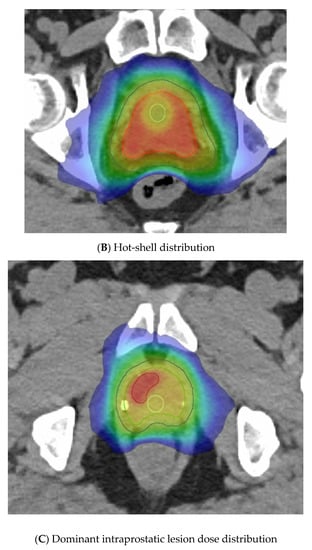

The last variable is the dose distribution, which varies between centres and trials. Some methods employ a relatively homogeneous whole-gland dose distribution (Figure 3A), whereas others aim to introduce inhomogeneity to replicate a brachytherapy implant with the purposeful aim of creating “hotspots” within defined volumes to receive up to 150% of the prescribed dose. These virtual volumes are intended to direct hotspots towards brachytherapy-type structures, such as spheres or cylinders. The CK platform can better replicate a virtual cylinder dose distribution compared to a standard LINAC due to the large number of non-coplanar angles used during delivery. A “hot shell” distribution aims to create hotspots along the prostate periphery with central urethra cooling (Figure 3B).

Figure 3.

Examples of virtual high-dose-rate brachytherapy boost radiotherapy dose distributions, with the colour gradient demonstrating 50% of the dose in blue up to the maximum doses in red. The green outline represents the prostate, the blue outline the planning target volume (PTV), yellow is the urethra, and burgundy the DIL, when outlined. (A) Homogenous distribution with 100% of the dose in red. (B) Hot-shell distribution showing the red 150% dose directed towards the prostate peripheral zone, with lime being the 100% dose. (C) Dominant intraprostatic lesion distribution, with the 150% dose in red directed towards the DIL and 100% dose in lime covering the PTV.

Another method gaining traction due to the FLAME RCT [66] is dominant intraprostatic lesion (DIL) boosting, where the boost dose is concentrated in the image-defined cancer volume (Figure 3C). FLAME used a simultaneous integrated boost and delivered a dose of up to 95 Gy in 35 fractions to the MRI DIL, with the whole prostate gland receiving 77 Gy in 35 fractions. A total of 84% of these patients were high risk and two thirds received ADT for up to 3 years. This trial reported improved 5 year biochemical disease-free survival (bcDFS), increasing from 85% to 92%, in the boost arm (HR: 0.45, 95% CI: 0.28 to 0.71, p < 0.001) without any significant increase in late GI or GU toxicities. The BOOSTER trial [50] integrated DIL boost with vHDRB, with three dose levels given. After the conventional radiotherapy dose of 46 Gy in 23 fractions, the boost used 20 Gy, 22 Gy, or 24 Gy to the prostate and, correspondingly, 25 Gy, 27.5 Gy, and 30 Gy to the DIL, all in two fractions. The highest dose of 30 Gy in two fractions was modelled to reflect the 150% isodose distribution of an HDR plan but preferentially directed towards the DIL.